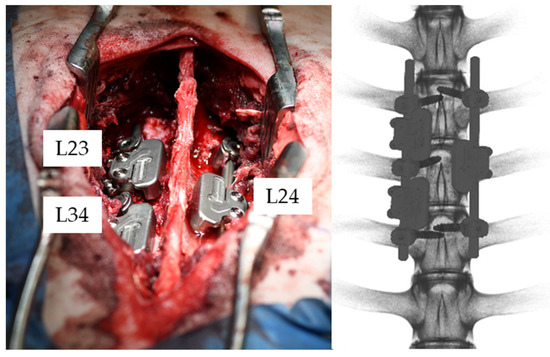

2.2. Animal Study